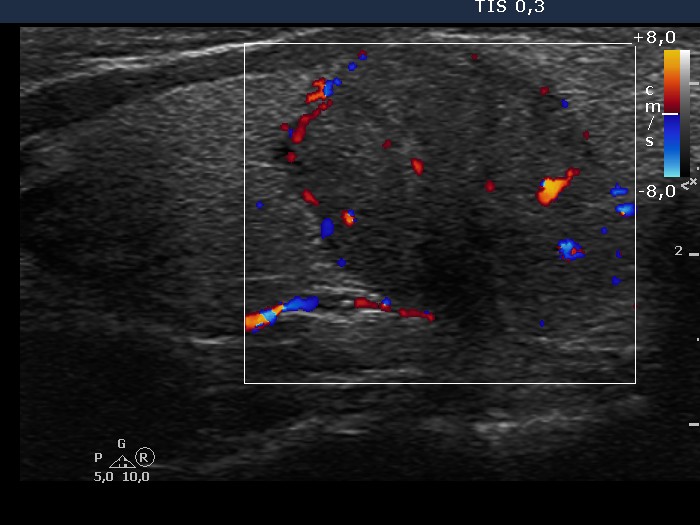

Left lobe, longitudinal scan, color Doppler mode. Both central and peripheral vascularization can be observed.